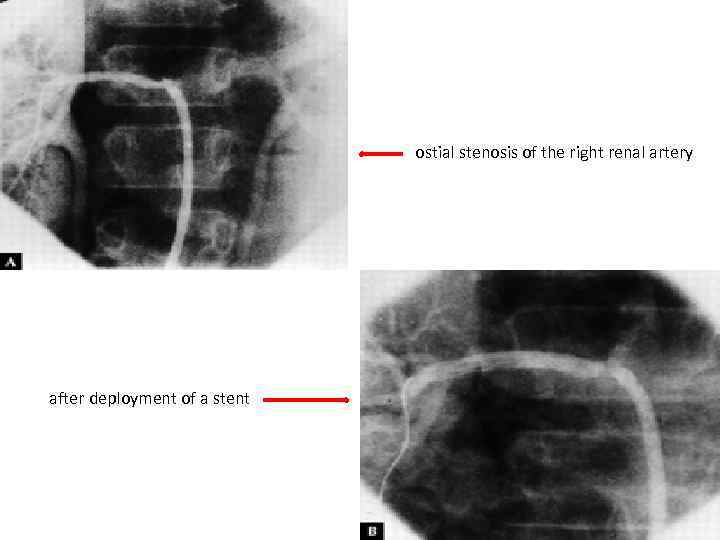

ostial stenosis of the right renal artery after deployment of a stent

Invasive treatment • HTN with critical RAS • Extremity claudication limiting daily activities • Cerebrovascular ischaemia or critical stenoses of ≥ 3 cerebral vessels • Moderate AR • Cardiac ischaemia with confirmed coronary involvement • Aneurysms Recommended at quiescent state - avoids complications (restenosis, anastamotic failure, thrombosis, haemorrhage, infection)